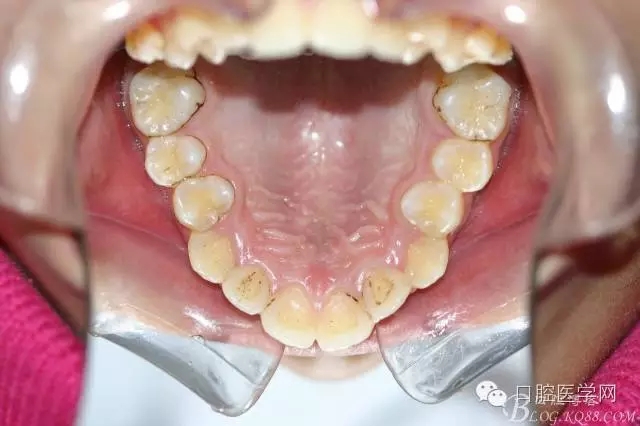

正畸查:替牙合。第一恒磨牙中性合。上牙弓尖圓型下牙弓方圓型。前牙覆合3度覆蓋7.5mm。下前牙咬到上舌側(cè)牙齦。上頜擁擠4.0mm,下頜擁擠

3.0mm。上頜稍前突下頜后縮,上下唇前突,上前牙覆蓋下唇,下唇外翻。面下三分之一過短,頦唇溝明顯,開唇露齒,頦饜窩明顯。顳下頜關(guān)節(jié)開閉口無彈響,無壓痛,開口型開口度正常。

正畸前照片: